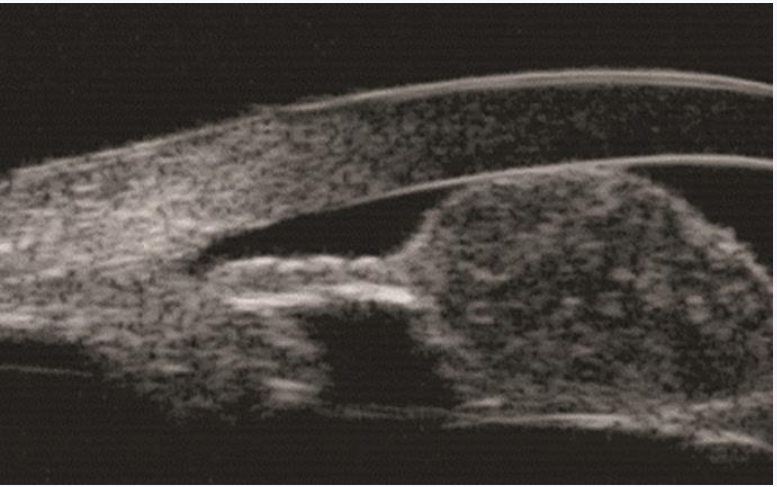

1周后患者复诊,查体:视力右眼0.7,左眼1.0,眼压右眼11mmHg,左眼15mmHg。右眼角膜清,前房中深,瞳孔圆,直径约3mm,对光反射存在,颞上方虹膜实性占位性病变大小未见明显改变,肿物表面出血较前吸收,色素脱失较前加重,前房白色絮状渗出明显吸收(图4)。右眼眼底及左眼查体同前。眼部UBM示右眼颞上方虹膜可见不规则形实性病变,大小约2.88mm×3.80mm×1.90mm,边界尚清晰,内回声不均匀,部分病变与角膜及晶状体前囊相贴,颞侧及下方房角内可见团条状回声,部分与虹膜相连;CDI示右眼颞上方虹膜实性占位性病变大小约3.5mm×2.3mm×1.4mm,边界欠均匀,内回声不均匀,CDFI病变内未探及明显血流信号;眼眶MRI示颞侧虹膜区见条状等T1、略短T2信号影,边缘不清,大小约2mm,增强后可见强化;胸部X线、血尿常规、CRP、生化常规、凝血四项、免疫四项、T-SPOT结核杆菌γ-干扰素释放试验、抗链O、抗核抗体(ANA)、TORCH特异性抗体检查均未见明显异常。

图3 CDI显示右眼颞上方虹膜实性占位性病变